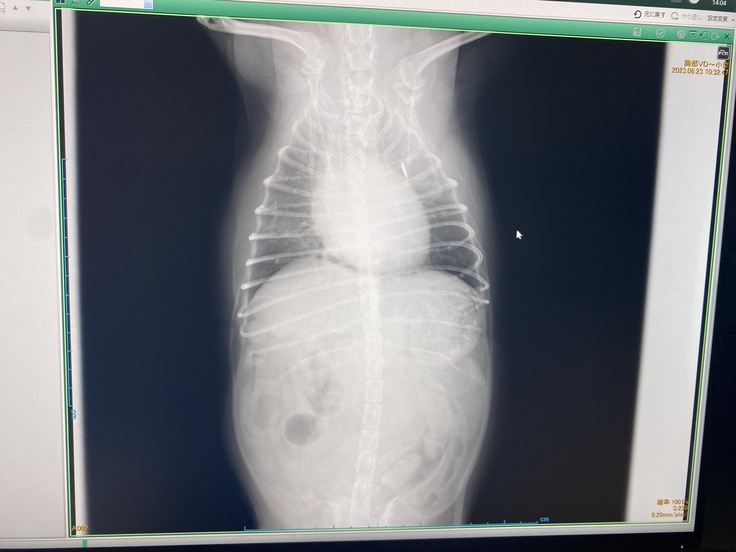

▼レントゲンの写真

恐れていた事態になってしまったとショックが隠しきれませんでした。

病状が進行していくと呼吸困難になることが何度もあり、入退院を繰り返しながら、苦しい状態と戦わなければいけない。

疲れていても横になって眠ることが出来ず、伏せの状態で気を失うように眠りにつく日々になるようです。